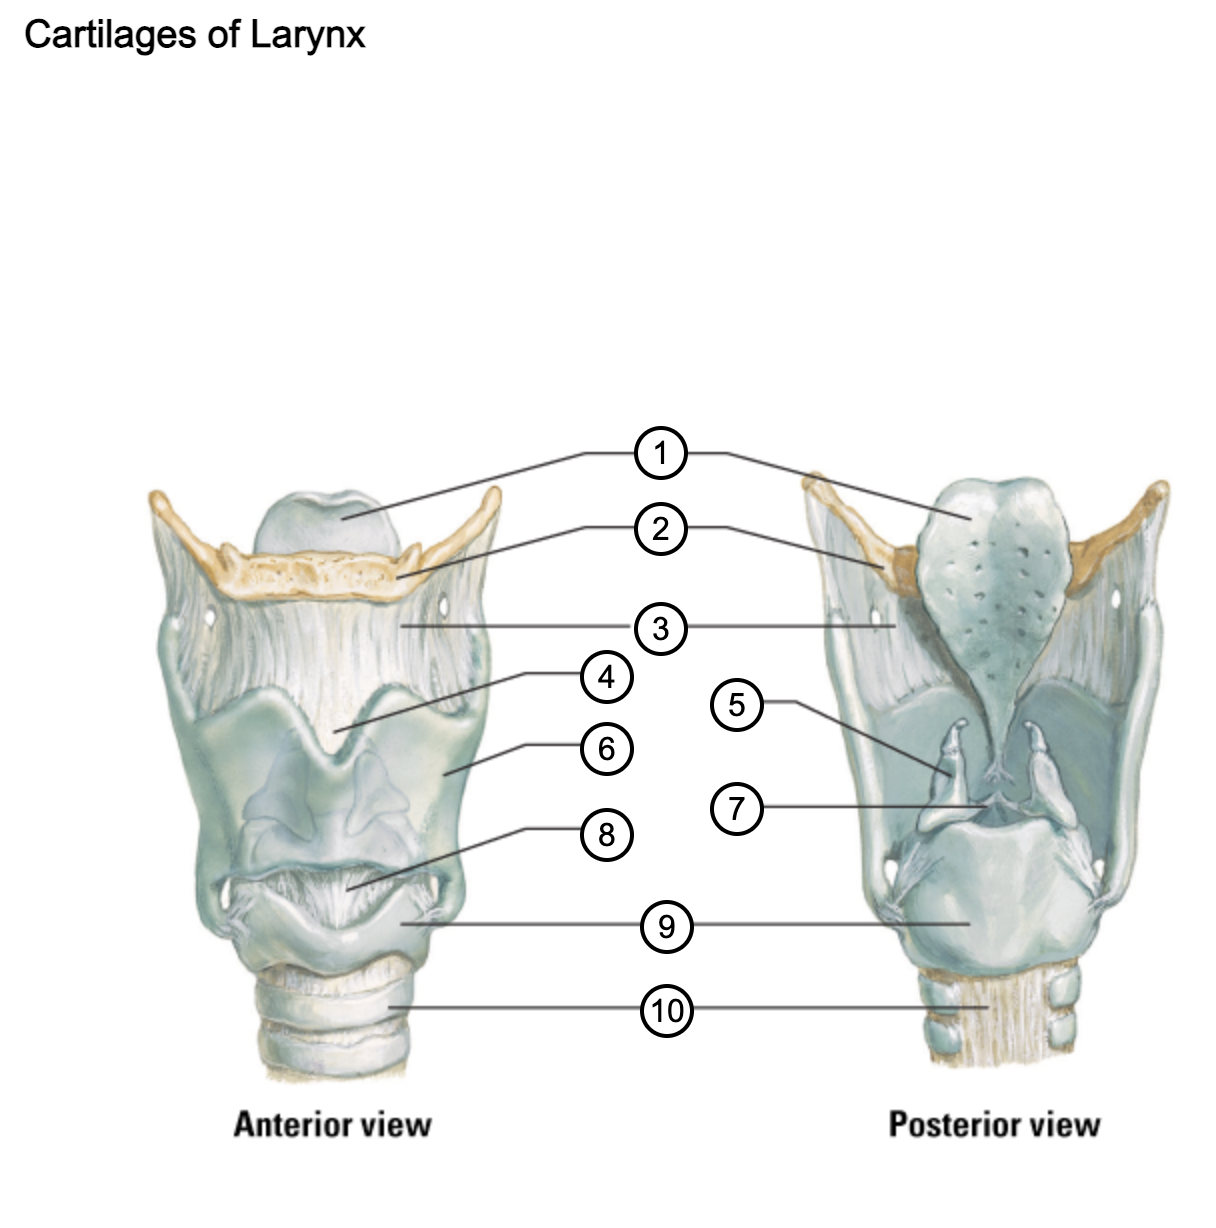

1

epiglottis

2

hyoid bone

3

thyrohyoid membrane

4

superior thyroid notch

5

arytenoid cartilage

6

lamina of thyroid cartilage

7

vocal ligament

8

median cricothyroid ligament

9

cricoid cartilage

10

trachea